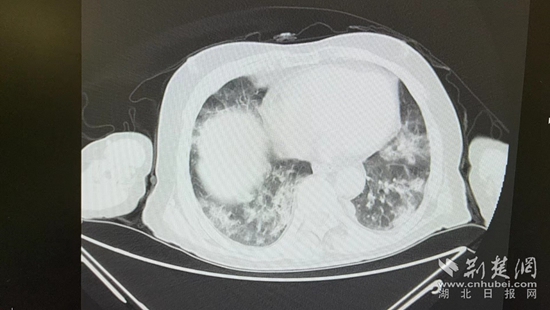

病情的突然惡化,會(huì)不會(huì)與近期的新冠病毒感染有關(guān)?雖然家屬反映,曾多次在家自測(cè)抗原正常,但徐濤還是力排眾議,說(shuō)服老人進(jìn)行核酸檢測(cè)和肺部CT檢查。結(jié)果顯示核酸陽(yáng)性,60%白肺,結(jié)合老人的表現(xiàn),這正是一例典型的老年人“沉默性肺炎”。

胸部CT片。通訊員 供圖